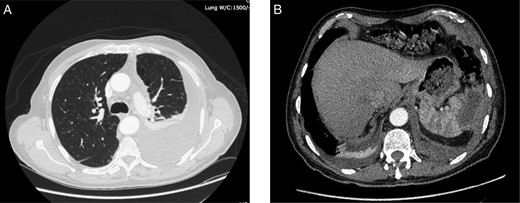

On admission, physical examination revealed normal vital signs and decreased breath sounds over the right pulmonary base as well as diffuse abdominal tenderness that was worse over the left hypochondrium. Blood culture samples as well as a complete blood count that revealed a normal hemoglobin and white cell count were taken. A CT scan confirmed the previously mentioned findings (Fig. 1). The patient was started on the same i.v. antibiotics he had been receiving (meropenem) and then taken to the operating room (OR) for video-assisted thoracoscopic lung decortication/pleurectomy. General surgery was then asked to assess the splenic abscess and, in consultation with interventional radiology, chose to treat conservatively. Two days later, the antibiotic regimen was simplified to i.v. ertapenem. After 4 days of this management, a new CT showed that the abscess had grown in size and had gas within it (Fig. 2). The decision was made to take the patient to the OR for a laparoscopic splenectomy.

CT scan taken 5 days after admission demonstrating an increase in the size of the splenic abscess as well as the presence of gas within its walls (arrow).